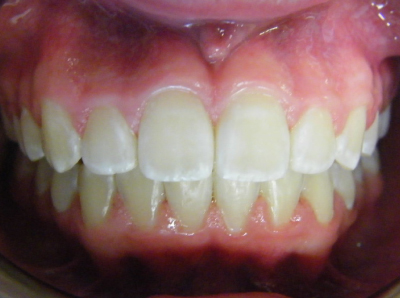

The first two sets of photos below are the before and after photos of a patient who had expansion of the upper jaw followed by upper and lower fixed braces. The third set of photos shows a patient with an expansion plate bonded to the upper teeth and lower fixed braces.